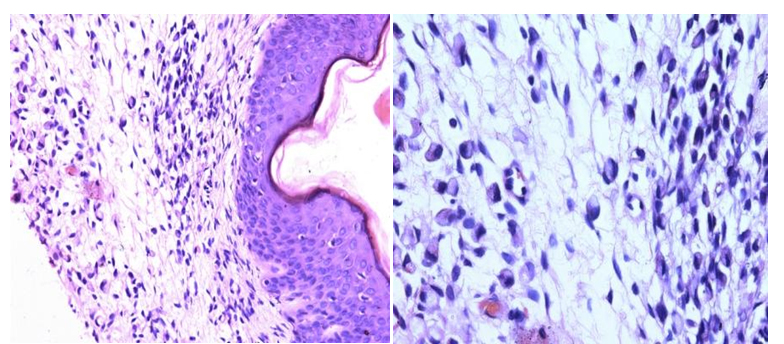

A 45 year old male came to the skin OPD with complain of brownish discoloration of abdominal skin with itching since 8 months and nodular skin eruptions in the abdomen since 4 months (Figure 1). He was provisionally diagnosed with allergic dermatitis and treated with topical steroid ointment and systemic anti-allergic drugs but without any response. After four weeks, skin biopsy was taken which revealed signet ring cell carcinoma which stained positive for PAS and cytokeratin (Figures 2a and 2b). Patient was referred to the Department of Surgery. On examination there was dark brownish discolouration and thickening of skin in mid and lower abdomen anteriorly and at the back. There were multiple, small, skin colored, nontender, firm nodules adherent to the overlying skin in right paraumbilical region over an area of 5 x 5 cm and on the left flank in 1 x 1 cm area. There was no palpable lump or organomegaly. On abdominal ultrasound, mural thickening of stomach was seen. Contrast enhanced CT scan of the abdomen showed diffuse thickening of antral and body regions of the stomach suggestive of carcinoma of stomach. Upper GI endoscopy revealed thickened gastric wall in body and antrum, biopsy was taken which was suggestive of moderately differentiated adenocarcinoma. Subsequently, the patient developed nausea and abdominal pain. In view of advanced disease, the patient was given palliative chemotherapy (ECF regimen). Epirubicin and Carboplatin was given on day 1 followed by daily infusion of 5-FU for 21 days. However, his condition deteriorated and he died within four months of his presentation.

Figure 2. a. Microphotograph showing epidermis covered dermis revealing infiltration by signet ring cells (H & E x 20X). b. Microphotograph showing cells with abundant amount of pale pink clear cytoplasm with nucleus pushed to periphery (H & E x 40X).